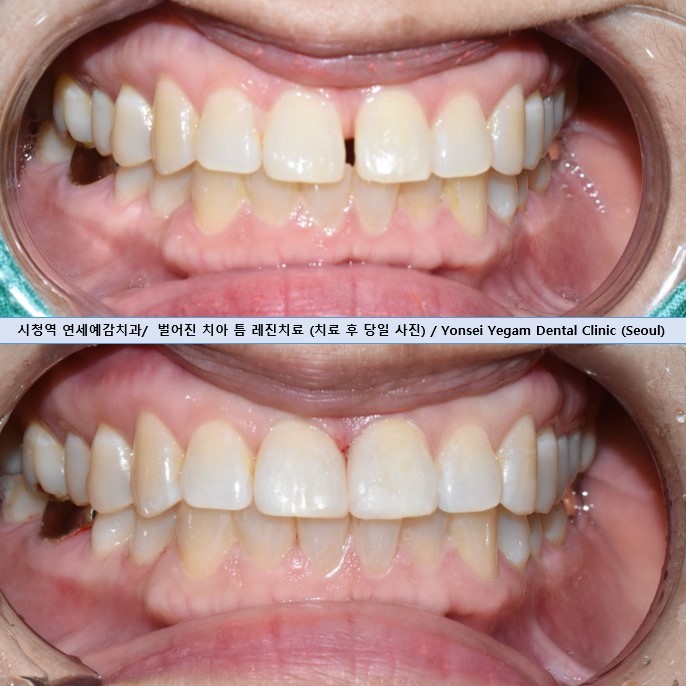

다른 치과에서 교정 후에도 앞니가 벌어져서 교정을 포기하신 50대 환자분입니다.

레진치료를 원하여 레진으로 진행하였습니다.

바로 당일에 치료가 끝나며,

치료 후 몇시간 기다릴 필요없이 바로 식사하실 수 있습니다.

이렇게 1시간안에 평생 고민거리를 해결하게 되어

환자분이 너무 기뻐하셨습니다.

만약 이번 케이스처럼 저렇게 정중앙에 공간이 있는 경우 위사진과 같이 공간을 1/2씩 나누어

두 치아에 각각 레진이 들어가야 하므로

앞니사이벌어진 공간 레진에 대한 비용은 30만원*2=60만원(이분은 첫시술)이 되겠습니다.